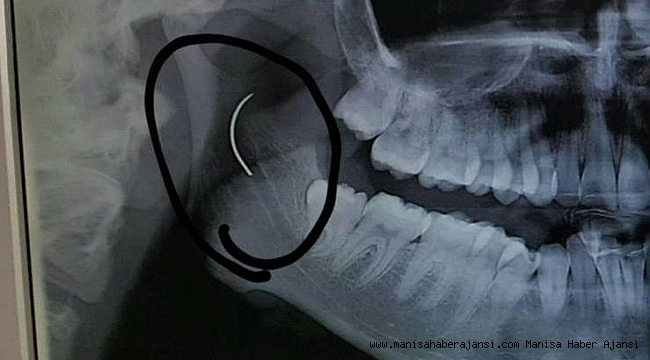

Soma Devlet Hastanesi'nde bademcik şikayetiyle 1999 yılında ameliyat olan Meltem Cansız'ın boğazında iğne unutuldu. 18 yıl boyunca boğazında iğne ile yaşayan ve şu anda 21 yaşında olan Meltem Cansız'ın tüm hayatı acı ve ağrılarla geçti. Boğazındaki iğnenin acıları günden güne yıldan yıla artan Meltem Cansız, 11 yıl sonra 14 yaşında iğnenin fark edilmesiyle Ege Üniversitesi'nde bıçak altına yattı ancak ameliyatı başarısız geçti. Lise öğreniminden sonra sağlık sorunları nedeniyle üniversiteye hazırlanamayan Meltem Cansız, acılarına rağmen yılmadı sabırla bekledi ve geçirdiği başarılı ameliyatla o iğneden 18 yıl sonra kurtuldu.

Boğazındaki iğneyle geçen 18 yılını anlatan Meltem Cansız, "3 yaşında geçirdiğim bademcik ameliyatında iğne boğazımda unutulmuş. Daha sonra iğneden dolayı 11 yıl sonra 14 yaşındayken kulak rahatsızlığım ortaya çıktı. Kafamın sağ tarafı ağrımaya başladı. Doktora gittik, hiçbir şey olmadığını söylediler. Sonrasında beni MR çekilmek üzere Akhisar'a yönlendirdi. Gecenin bir vakti MR'a girdim. Ancak bir türlü çekemediler. Benim üzerimde toka vs. metal bir şey olduğunu söylediler baktılar ancak bir şey yoktu. Üç yada dört defa MR'a girdim. Ancak bir türlü çekemediler. Sonra doktorumuz röntgene yönlendirdi. Röntgen görüntüsünde ameliyattan kalma bir çengelli iğnenin boğazımda olduğu görüldü. Bunun için beni Ege Üniversitesi'ne sevk ettiler. Burada doktorlar bu ameliyatı yapabileceklerini ancak riskinin çok olduğunu söylediler. Biz yine de kabul ettik. 1,5 saatlik operasyon geçirdim ancak iğneyi bulmadıklarını söylediler. 2 sene kadar araştırma yaptık. Birçok hastaneyle görüştük. Ancak ayağımda bir rahatsızlık meydana geldi. Ayağım için Ege Üniversitesi'ne gittik. Tekrardan beni ameliyat eden doktorumla görüştüm. 'Seni ben ameliyat ettim, tekrardan buna kalkışamam' dedi. MR'a da giremezsin dediler. 'Sen bununla yaşamayı öğren' en azından bunun için çabalama alınmaması daha iyi dediler. Ben daha genç bir kızım sonuçla bu iğneyle ömür boyu yaşayamazdım. Yaşanan bu olumsuzların ardından araştırmalarımız neticesinde en son İzmir'de özel bir hastaneye gittik. Oradaki doktorum Çağlar Çallı bey bana umut verdi. 'Bu iğneyi alacağız' dedi. İnancımı kaybetmedim, sonucun ne olacağını bilmeden girdim ben o ameliyata. Ölüm, felç olma riskim çok fazlaydı. 'Yaşayamayabilirsin' dediler, biz bile bile lades dedik. Sonucu da güzel oldu" dedi.

Ege Üniversitesi'ne gittiklerini belirten baba Cansız, iğnenin şah damarına çok yakın olduğunun söylendiğini belirterek şunları söyledi: "Doktorlar çok tehlikeli bir ameliyat olacağını yanlış ya da en ufak bir hatada kızımızın bir tarafının felç kalabileceğini veya hayatını kaybedebileceğini söylediler. Biz bu riski göze alarak ameliyata müsaade ettik. Fakat iğneyi görüldüğü yerde bulamadıklarını söyleyerek alamadılar. Sonra İzmir Çiğli'de özel bir hastanede denedik. Kendisine binlerce kez teşekkür. Allah razı olsun. Çocuğumun boğazındaki iğneyi aldı. Dünyalar bizim oldu."